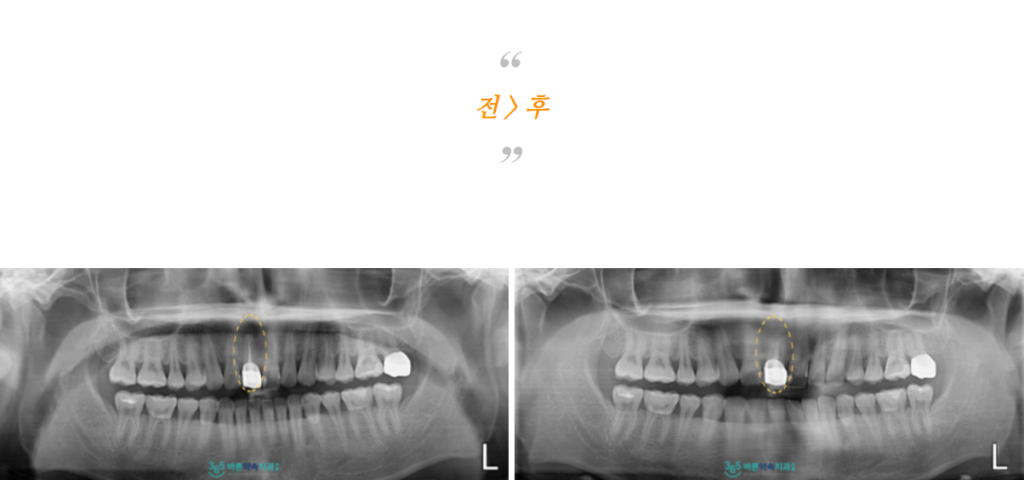

치근단 절제술 후 1주일 정도 뒤

잇몸뼈 회복 상태를 확인하기 위해

파노라마와 3D CT를 촬영해 보았더니

염증이 깨끗하게 제거가 되었고

뿌리끝이 단단히 메워져 있는 것을

확인할 수 있었습니다.

환자분께서는 처음 내원 당시

뿌리 끝에 염증이 있는 사진을 같이 보시고는

치아를 뽑아야 하는 건 아닐까

걱정이 많으셨는데

자연치아를 살릴 수 있는 치료로

치아도 지키고

통증도 사라져 만족해하셨습니다.